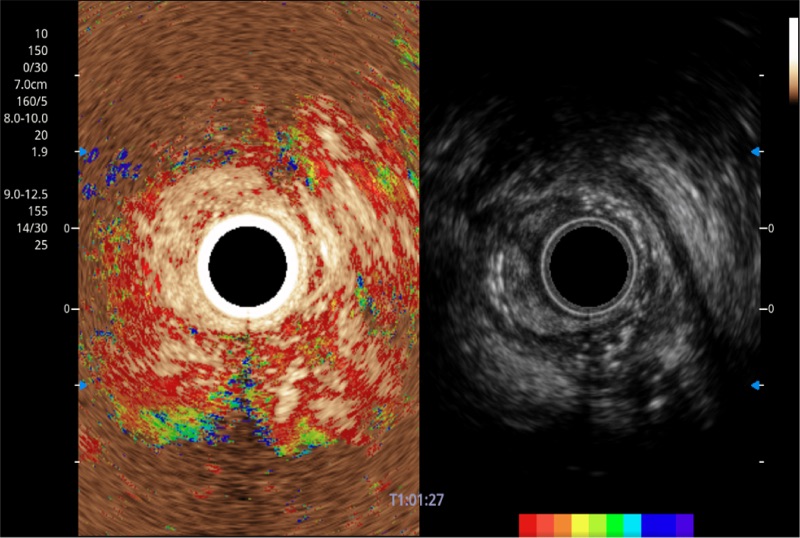

肝左叶和肝静脉的横截面